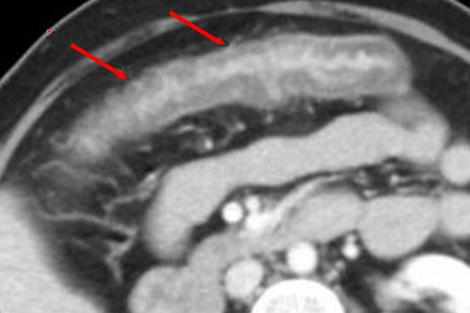

Image radiologique de lavement baryte du

colite ischemique est empreinte du doight par epaisissement

oeudemateuse des haustral du colon , image de

spasme du colon + ulceration en forme scie ou image de

stricture par fibrosis du colon .

Image radiologique de

lavement baryte du colon transverse : Image de

empreinte de pouce du colon se voyait si net au

colon transverse ( fleche rouge ) avec image

d' augementation de contraction du colon |